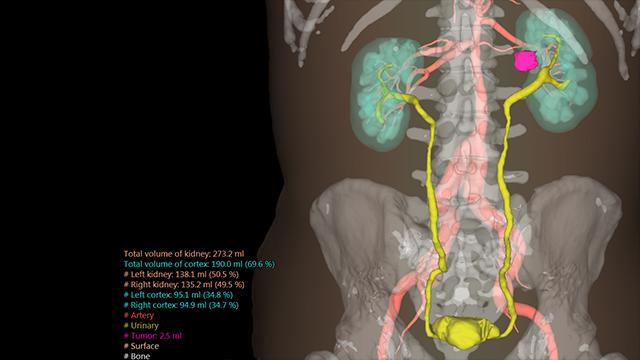

ANYTHINK 经导管主动脉瓣膜置换术分析系统